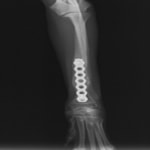

LCPは、スクリュー(ネジ)とプレート(金属の板)をロックする特殊な構造により骨折部位を固定する新しい世代のプレートシステムです。ひとつのホールでロッキングスクリューとスタンダードスクリューの使用を選択できるユニークな構造をしているため、骨折断端間の圧迫を目的とした従来型プレート固定法に加え、高い角度安定性を有するロッキングスクリューを用いた固定法の選択が可能です。従来のプレートシステムでは困難だった部分の骨折や癒合不全の症例に高い治療効果をもたらします。

Locking compression plate system の特徴

1.骨膜上の血行障害は最小限

2.高い角度安定性

3.プレート設置時の整復位喪失の防止

4.スクリューのルースニング(ゆるみ)の防止

5.コンビネーションホール

6.粗鬆骨における固定性の向上

7.1.5mmと薄いプレートのため、超小型犬にも使用しやすい

8.抜去が不要となることが多い